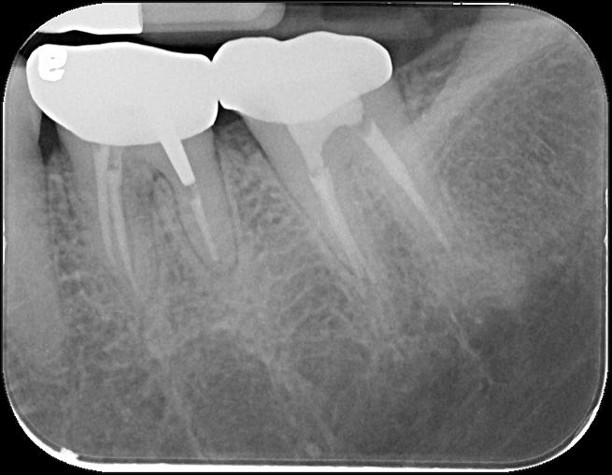

治療前,原根管治療已再污染

大臼齒顯微根管治療